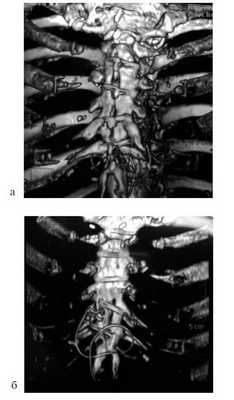

Следующий этап обработки - это сегментация 3D-серошкального изображения, которая заключается в выделении определенных областей по однородности каких-либо их характеристик и построении поверхностей этих областей. Такое сегментированное 3D-изображение по сути является анатомической моделью исследуемой области. Следовательно, абстракция изображения достигается за счет получения численных значений характеристик визуализируемых тканей - построения объемных анатомических моделей исследуемых органов и структур тела человека (рис. 2). Рисунок 2. Мультиспиральные компьютерные томограммы с 3D-реконструкцией (больная Г., 57 лет). а - вид грудной клетки спереди. В нижней трети грудины - витки тонкой проволоки (электрода), «ныряющего» загрудинно; б - вид передней грудной стенки сзади. Загрудинное расположение проволочного электрода.

При МСКТ грудной клетки с контрастным усилением и мультипланарной реконструкции отмечено поражение нижней трети тела грудины, мечевидного отростка с вовлечением в воспалительный процесс тонкой проволоки - электрода, имеющего сложный ход, уходящего за грудину.